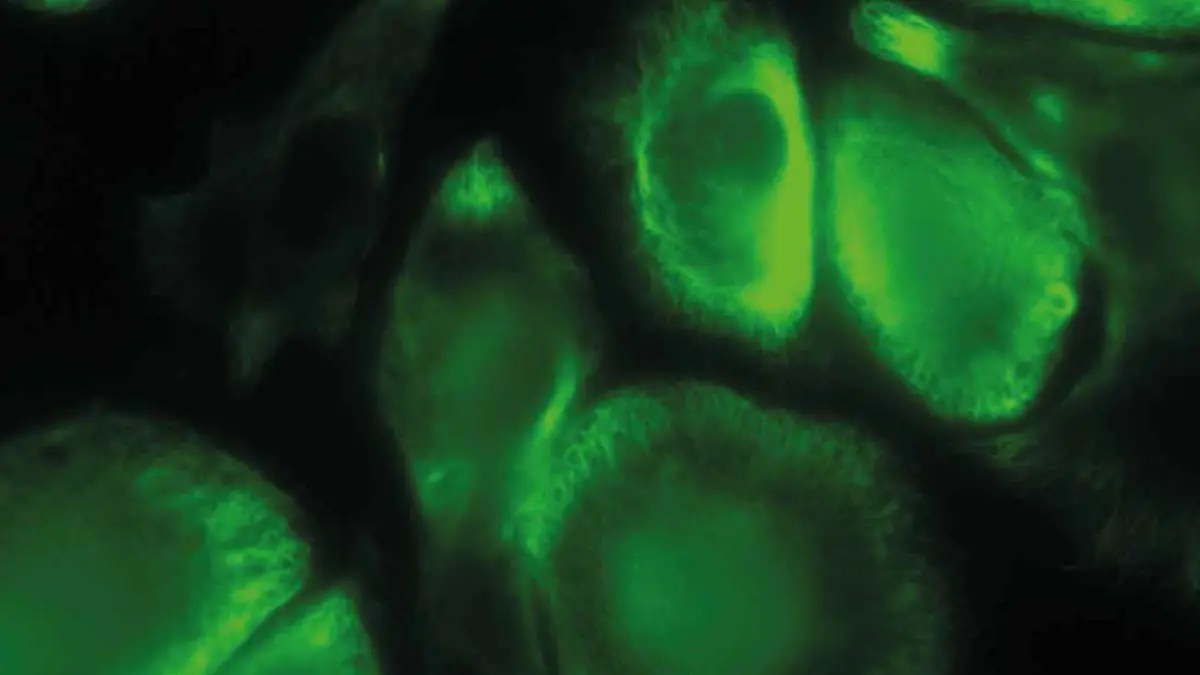

Der Flug ins All von Alexander Gerst dient in erster Linie der Forschung. Und an Ideen mangelt es den Wissenschaftlern nicht: Allein 50 Experimente mit deutscher Beteiligung wird der deutsche Astronaut durchführen. Hier eine Auswahl.